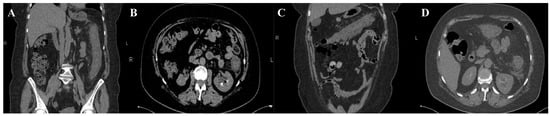

Microbiological investigations ruled out Clostridium difficile, Shigella, Salmonella, and parasitic involvement, and a PCR-based multiplex pathogen GI test detected Shiga-like toxin-producing Escherichia coli (STEC) stx1/stx2 genes. The STEC serotype and subtype could not be determined. The abdominal CT revealed a spastic transverse and descendent large intestine with a thickened circumferential mucosa, suggestive of an inflammatory and infectious process, which progressed over the following days (Figure 1 and Figure 2).

On the third day, the patient underwent a second abdominal CT scan, which showed extensive colonic lesions up to the hepatic flexure and down to the sigmoid and rectum (Figure 2), preserving the mesenteric artery with contrast medium. This picture was compatible with the micro-ischemic lesions found in infectious ischemic colitis [6,7].

Tomographic features very suggestive of bacterial colitis are (1) continuous distribution, (2) an empty colon, (3) the absence of fat stranding, (4) the absence of a “comb” sign, and (5) the absence of enlarged lymph nodes [2]. According to these criteria, our patient had extensive and continuous distribution, collapsed intestines, and the absence of enlarged lymph nodes. However, contrarily, she had pericolic fat stranding and an incomplete “comb” sign, which made the final diagnosis more difficult to determine.

Figure 1. First abdominal CT. Spastic large intestine, with thickened circumferential mucosa (blue arrow), up to 1.33 cm (B), and an incomplete “comb” sign (green arrow) (C). Coronal (A,C) and axial planes (B,D) respectively.